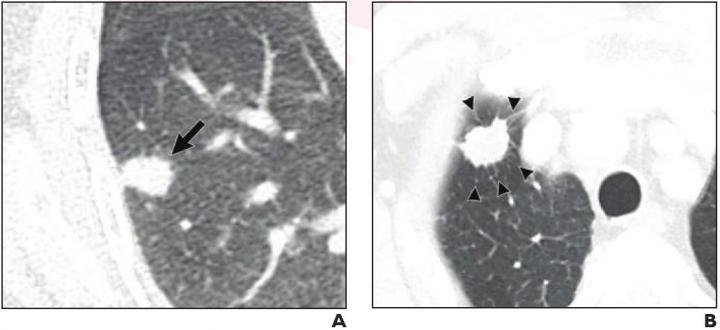

image: (A) 70-year-old woman with pulmonary adenocarcinoma who underwent sublobar resection without evidence for pLVI. 15-mm solid nodule with irregular margins present in right lower lobe (arrow). No tumor recurrence on 37-month follow-up. (B) 75-year-old man with pulmonary adenocarcinoma who underwent wedge resection that exhibited pLVI. 19-mm solid nodule with irregular margins and peritumoral interstitial thickening (arrowheads) present in right upper lobe. Ipsilateral mediastinal and hilar lymph node metastasis occurred after 5-month follow-up (not shown).

"Among such nodules," the authors of this AJR article continued, "peritumoral interstitial thickening (odds ratio=13.22) and pleural contact (odds ratio=2.45) were independently associated with pathologic lymphovascular invasion." Moreover, models incorporating these features independently predicted recurrence-free survival after sublobar resection (hazard ratio=5.37-6.05).